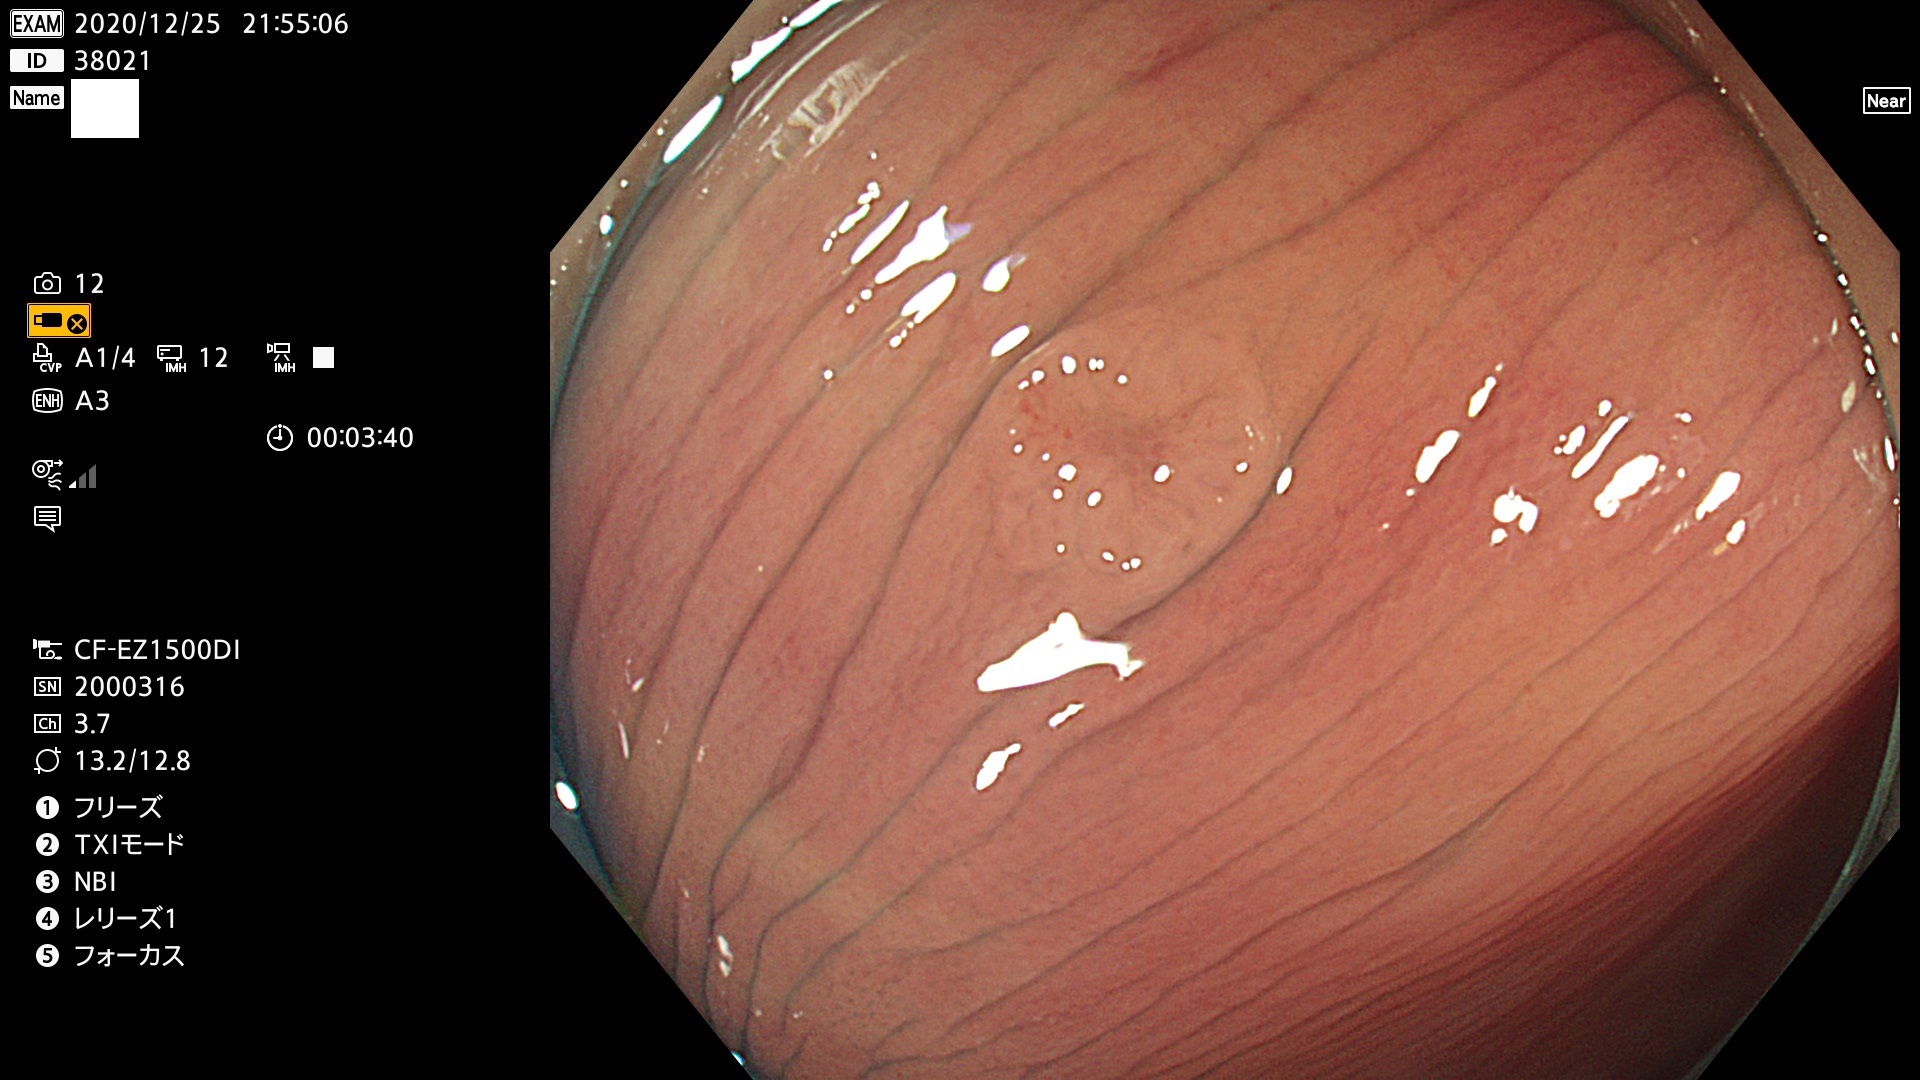

38001 38002 38003 38004 38006(SSAPのみ) 38007 38008 38009 38010 38012 38013 38014 38016 38018 38020 38021 38025 38026 38029 38032 38033 38034 38035 38036 38037(SSAPのみ) 38039 38043 38044 38048 38049 38050 38052 38055 38056 38057 38058 38059 38064(SSAPのみ) 38065 38068 38069 38070 38071 38072 38074 38075 38076 38078 38079 38080 38082 38083 38084 38085(SSAPのみ) 38086 38087 38088 38089 38090 38091 38092 38093 38094 38097 38098 38099

発見困難で危険性の高い平坦型病変(上記100名より抽出)